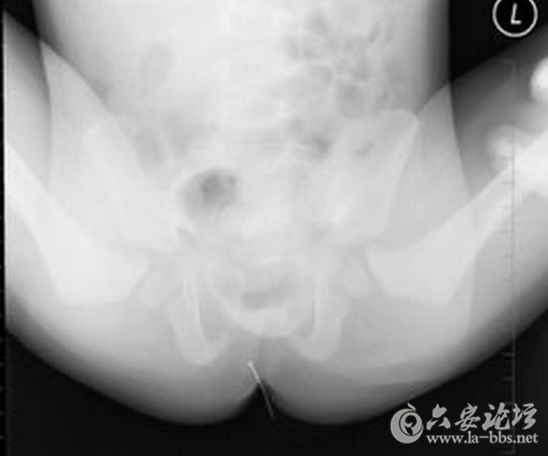

这些让人瞠目结舌的X光片,映射出了女人下体的那点儿事儿,对性有需求是好的,可是要是乱放东西,伤到身体,那可麻烦大了!

一根弯了的钢针?够疼的!